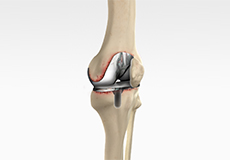

Total Knee Replacement

Total knee replacement, also called total knee arthroplasty, is a surgical procedure in which the worn out or damaged surfaces of the knee joint are removed and replaced with an artificial prosthesis.